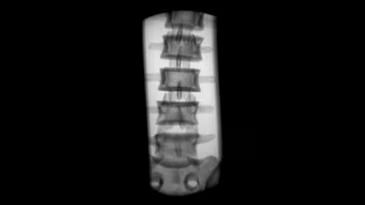

Brivo OEC 785 - это надёжная С-дуга, которая работает вместе с вами, эффективно устраняя сложности визуализации и позволяя хирургу сфокусироваться на пациенте. Отличительной чертой системы Brivo OEC 785 является высокое качество визуализации, на которое можно рассчитывать изо дня в день. Вы можете доверить технологиям GE Healthcare точное и эффективное получение чётких изображений, даже при низкой дозе. Автоматизированные смарт-функции Brivo OEC созданы, чтобы вы получали изображения высокого качества, даже в клинически сложных случаях. Подобно тому, как орлиный глаз может различить движение и малозаметные объекты, эта система делает упор на получение изображения высокой точности при любой степени клинической сложности.

- Четкая визуализация и клиническая надежность

Получение четких изображений с помощью «умной» цепи визуализации. - Удобная работа